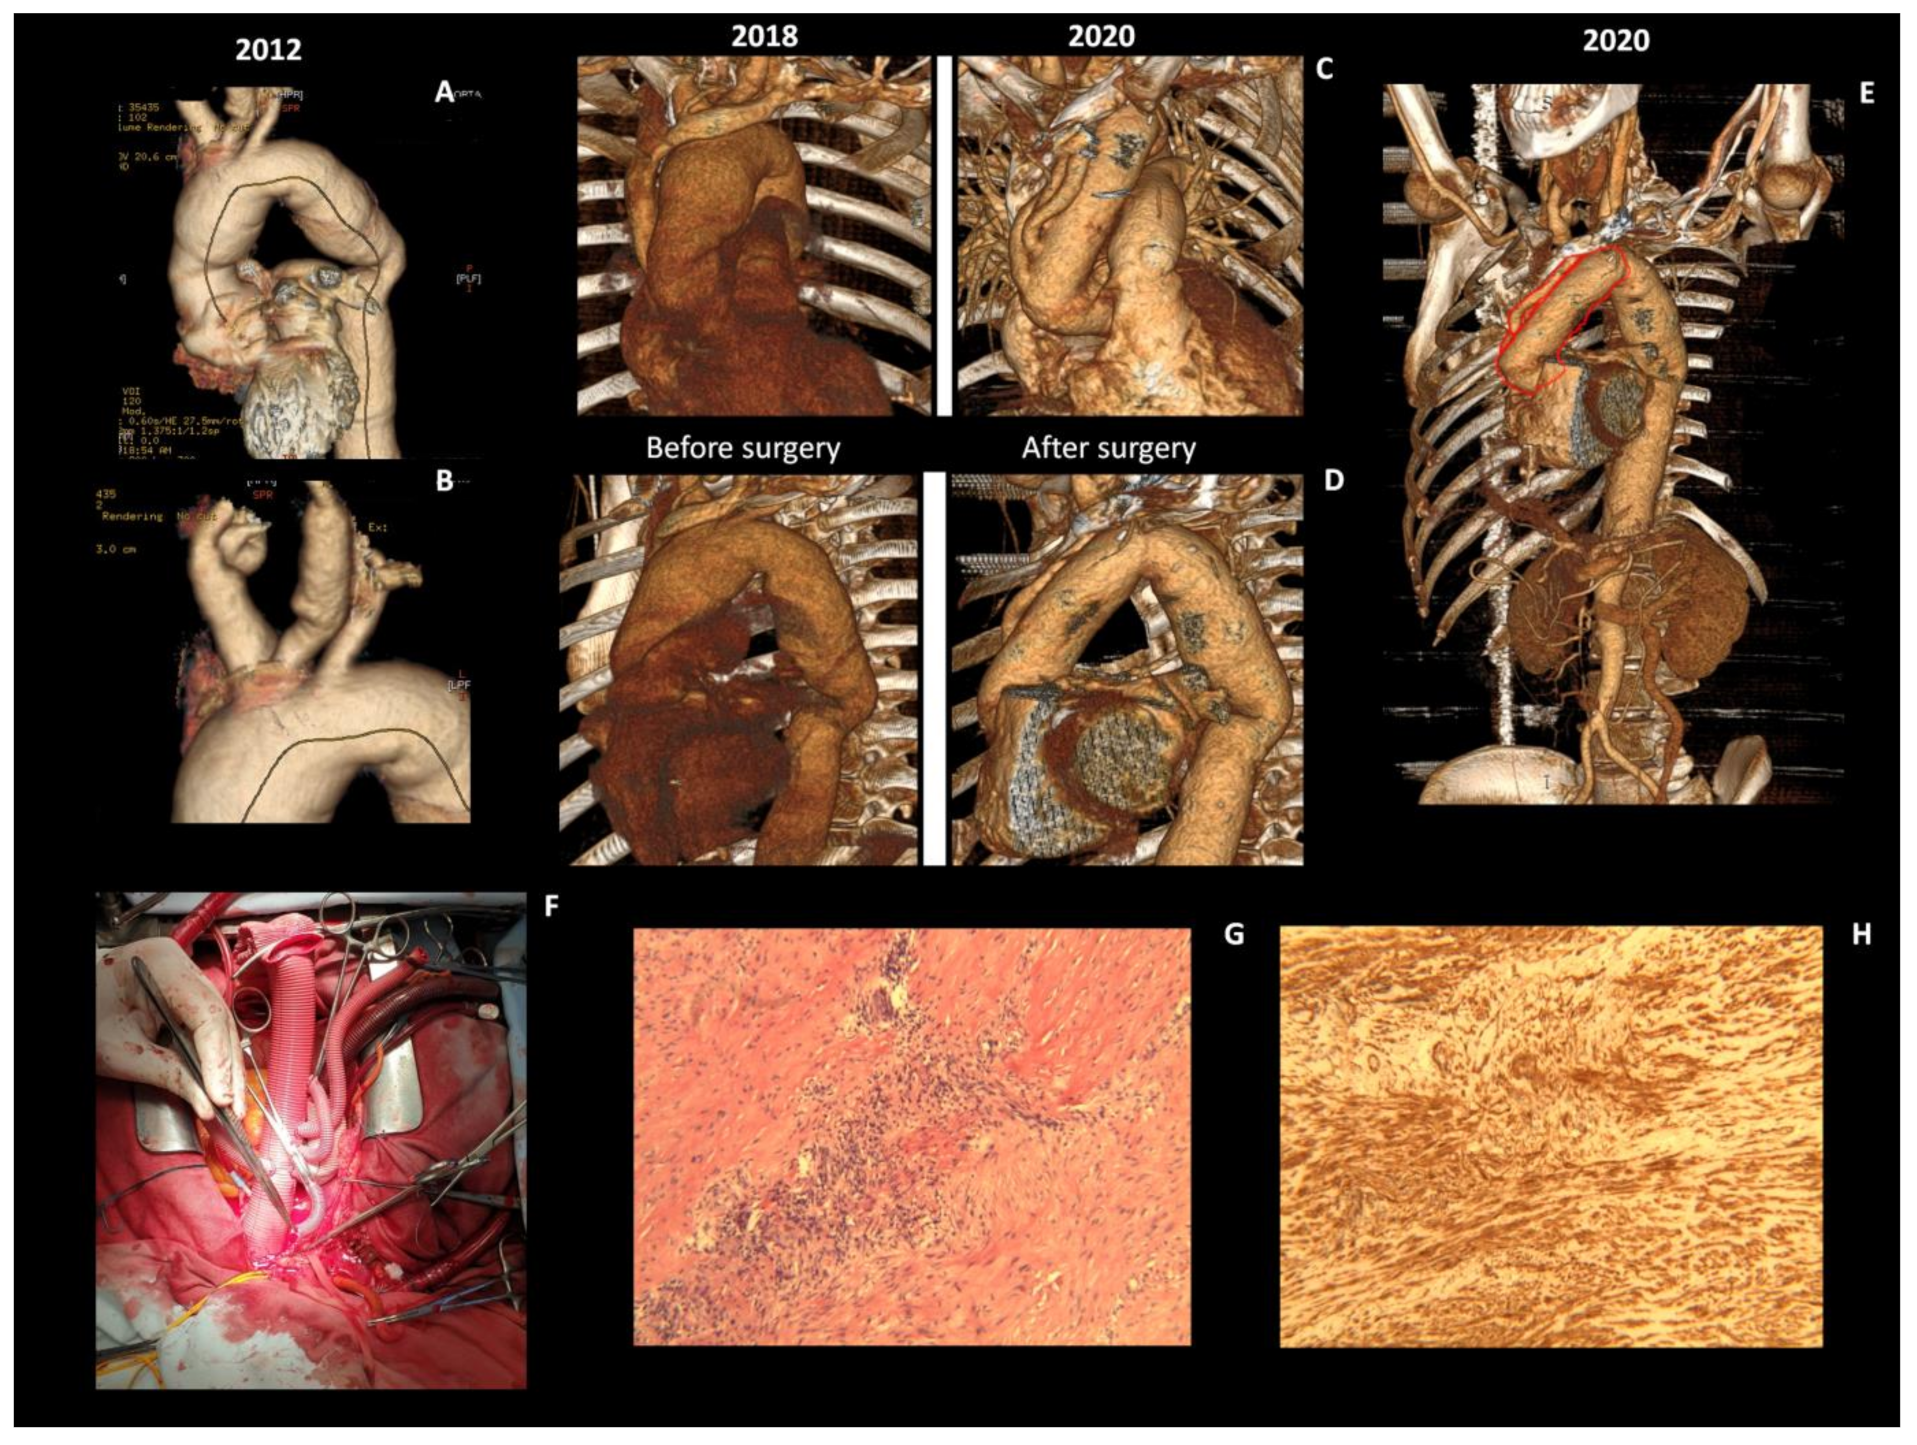

Major Aortic Reconstruction with the Replacement of Supra-Aortic Branches: Successful Surgical Treatment of Takayasu Arteritis Initially Presented as Congestive Heart Failure